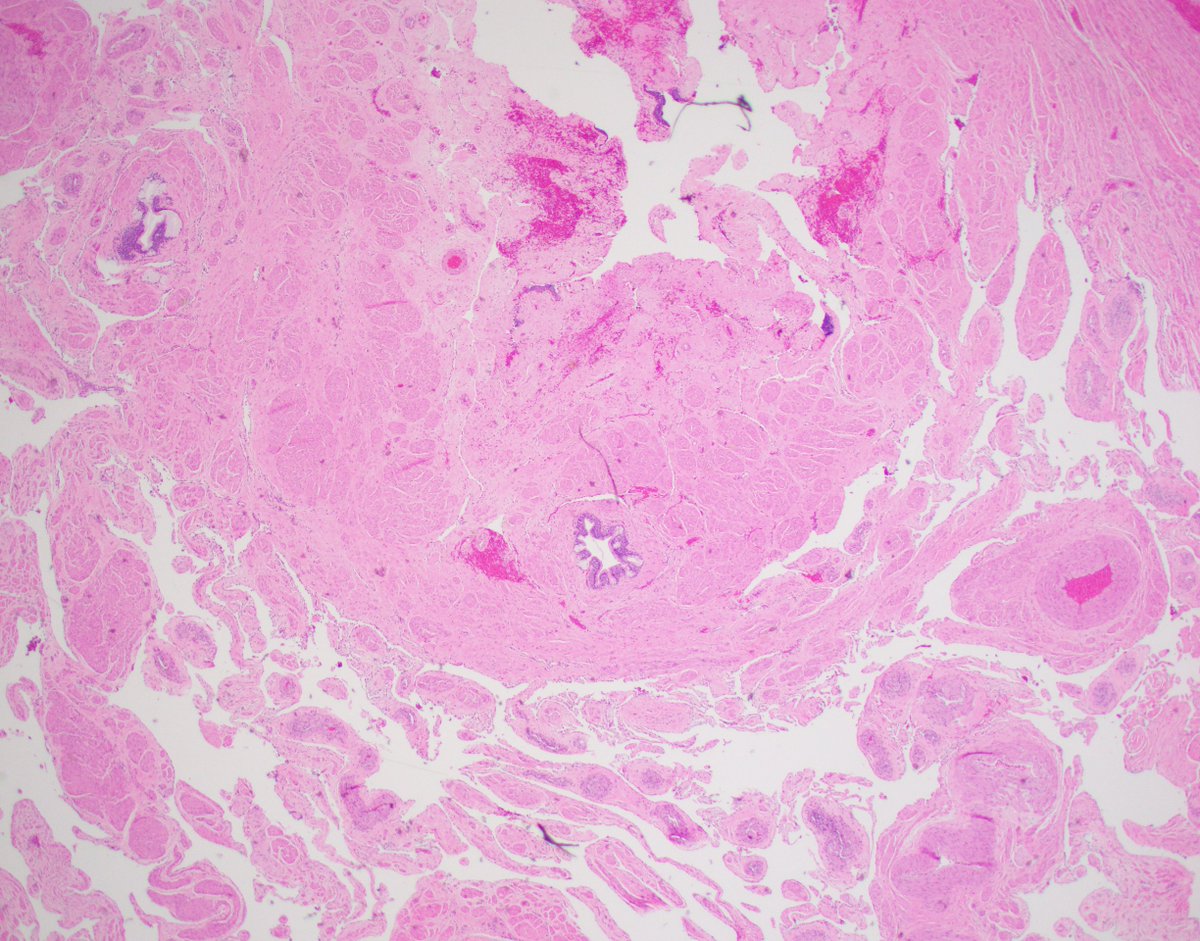

1/4 Dedicated to the memory of Dr Ondrej Hes x.com/GU_Path_Societ… Adult, medullary based kidney tumour - large discohesive polygonal, rhabdoid cells - multinucleated cells - cytoplasmic vacuoles #PathTwitter #PathResidents #Pathology #GUPath Ahmad Dhia GU Pathology Society (GUPS)